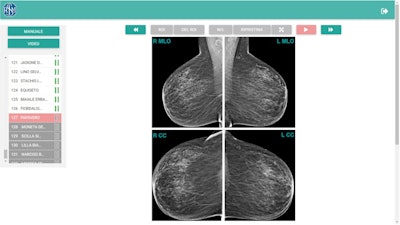

![Region-of-interest delineation in a magnified craniocaudal projection. No more than one region of interest can be placed on each projection. If a case is left with a region of interest placed on a mammographic projection, it will be classified as true positive if the region of interest matches the one previously delineated during dataset building for the actual presence of carcinoma; otherwise, the case will be classified as a false positive. To store the case as a negative one and move on to the next one, the reader can click on the button with white arrowheads on green background (shown at the right end in top figure [Example of mediolateral oblique projection magnification]). The case will be classified as true negative if carcinoma is not actually present, otherwise as a false negative.](https://img.auntminnieeurope.com/files/base/smg/all/image/2021/09/ame.2021_09_10_19_02_6235_2021_09_13_womens_insider_Figure3.png?auto=format%2Ccompress&fit=max&q=70&w=400)